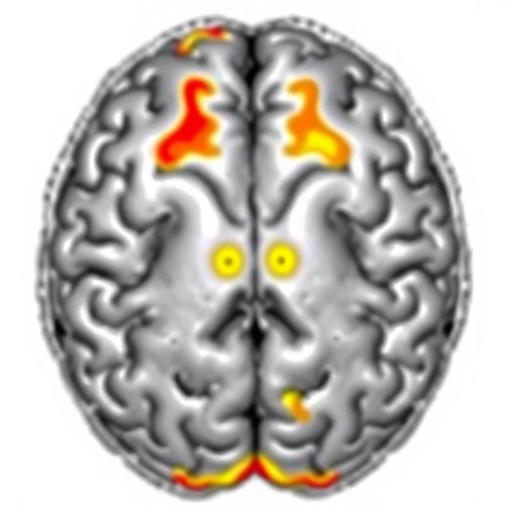

The neuroscience community stands on the brink of a transformative breakthrough in brain mapping with the introduction of NextBrain, a cutting-edge probabilistic human brain atlas engineered for unparalleled MRI segmentation. Unlike traditional brain atlases that offer static representations, NextBrain integrates probabilistic models with high-resolution imaging data, creating a dynamic, versatile tool tailored for both research and clinical applications. This innovation, unveiled in a recent study, represents not just an incremental advance but a fundamental leap forward in our capacity to visualize, analyze, and interpret human brain architecture at unprecedented granularity.

Of particular note is NextBrain’s robust Bayesian segmentation tool, a sophisticated algorithmic framework that leverages prior probabilistic knowledge to distinguish and segment brain regions automatically. This approach not only harnesses the power of next-generation imaging but also adapts seamlessly to diverse scanning conditions, including the challenging interface between ex vivo and in vivo data. Its compatibility with standard 1-mm isotropic scans ensures broad applicability, from high-field laboratory MRI systems to routine clinical imaging environments. By marrying rich probabilistic models with real-world imaging constraints, NextBrain sets a new standard for accurate, reproducible, and granular brain segmentation.